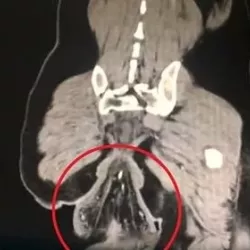

Врачи выяснили, что «сгустком» оказалась его прямая кишка.

Ректальный пролапс, по словам специалистов, действительно мог произойти из-за долгого сидения на унитазе. Лечащий врач мужчины рассказал, что у пациента были выявлены проблемы, начавшиеся несколько лет назад, но без должного лечения ситуация ухудшилась.